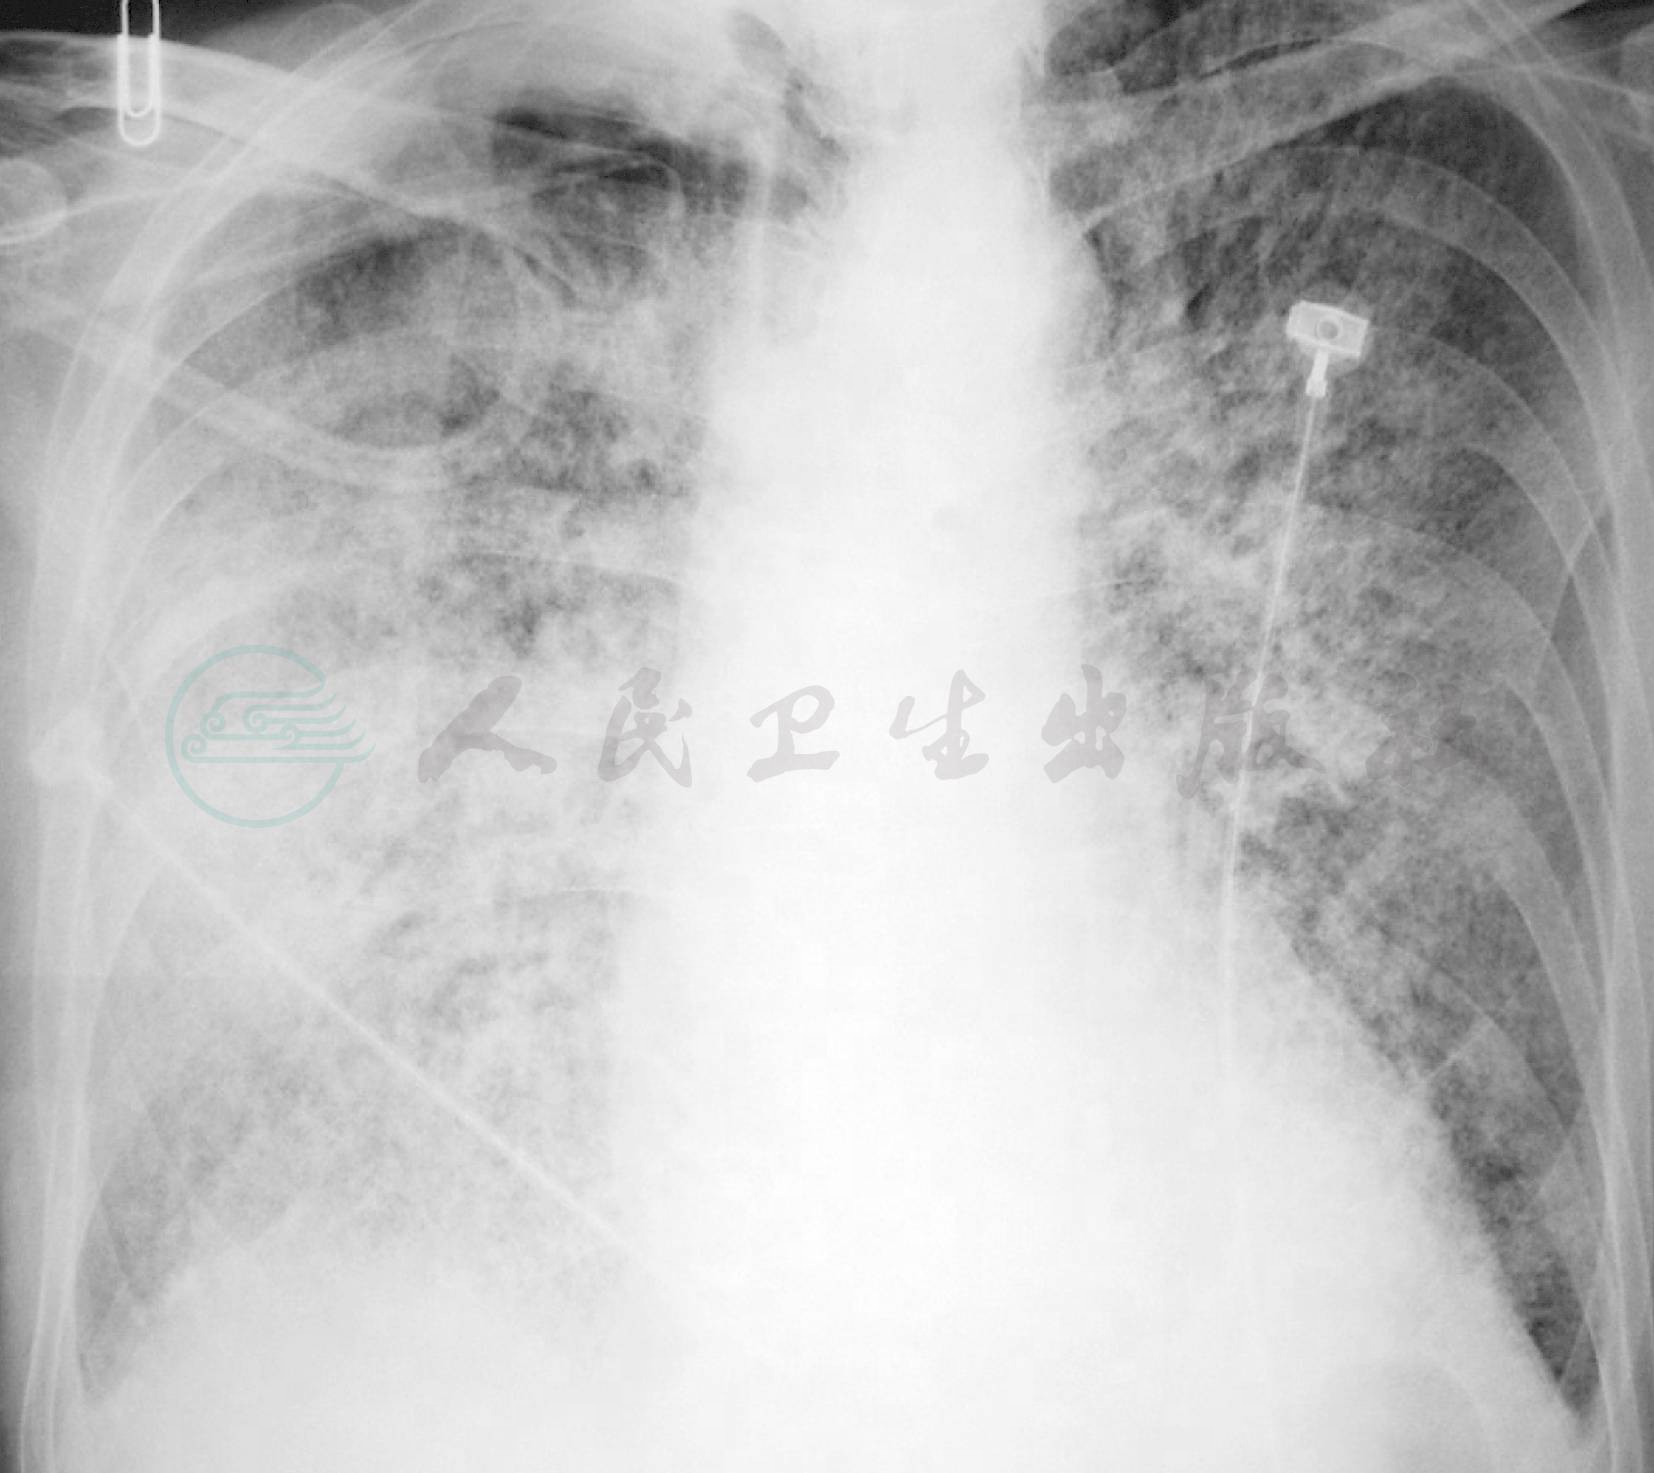

给予莫西沙星抗感染、无创呼吸机辅助通气等治疗效果不佳,患者仍发热,并出现咳血痰、呼吸困难、血红蛋白进行性下降至82g/L,复查胸部X线片示双肺多发斑片影病变进展迅速(图2,图3)。其他化验检查:

图2 2010年5月26日胸部X线片

双肺多发斑片影

图3 2010年6月14日胸部X线片

双肺多发斑片实变影,较前加重